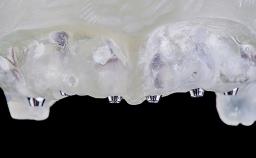

Rehabilitating an Edentulous Maxilla with a Fixed Dental Prosthesis Using a DSD-Guided Approach

A 60-year-old man was referred to the Center of Excellence for Prosthodontics and Implant Dentistry (CEPI) of the School of Dentistry of the University of São Paulo, Brazil for implant therapy. Anamnesis, clinical examination, and radiographs revealed esthetic and functional problems, the absence or structural compromise of various teeth (16–11, 21, 22, 24, 25, 37, 45, and 48), periodontal and endodontic problems (17 and 27), implant fracture (46), and occlusal disorders . The patient reported that he was undergoing treatment for cardiovascular diseases.